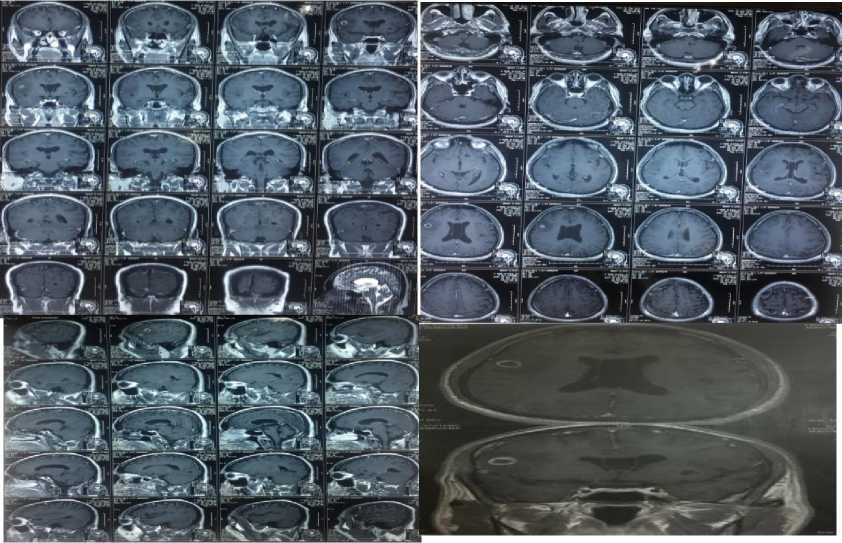

Pasien lupa nama-nama obat yang diminum selama perawatan saat itu. Hingga saat ini pasien masih meminum obat kejang itu namun terkadang tetap mengalami kejang dengan pola yang sama, sebanyak kurang lebih 3-4 kali dalam satu tahun. Obat yang diminum pasien hingga saat ini yaitu asam valproat 3x500mg peroral dan asam folat 2x1mg peroral. Hasil pemeriksaan EEG yang lalu dalam batas normal, hasil CT scan kepala dan MRI kepala dengan kontras dapat dilihat dibawah pada Gambar 1.

Pemeriksaan penunjang radiologi yang dilakukan yaitu CT scan kepala dan MRI kepala dengan pemberian kontras. Perbandingan gambar CT scan kepala tanggal 17 Juli 2010 dan 29 September 2017 dapat dilihat pada Gambar 2. Gambaran MRI Kepala dengan kontras ditunjukkan pada Gambar 3.

Gambar 1. MRI Kepala dengan kontras (20 Oktober 2010), tampak lesi multipel (berjumlah 7-8) lesi kistik isointens, terdapat eccentric hyperintense 2-5 mm scolex dengan pea-in-the pod appearance menunjukkan gambaran neurosistiserkosis. Lesi pada girus frontotemporal kanan disertai adjacent perifokal edema dan enhancing cyst wall. Gambaran MRI menunjang suatu Neurosistiserkosis.

Gambar 2. (kiri) CT-Scan kepala tanpa kontras (17 Juli 2010) dan (kanan) CT-Scan kepala tanpa kontras 29 September 2017. CT-Scan pertama terdapat gambaran hipodens multipel di daerah frontal

kanan dan kiri, parietal kiri dan oksipital kanan

Gambar 3. MRI Kepala dengan kontras (11 Oktober 2017) tampak lesi hipointens (T1W) didaerah parietal kanan menjadi hiperintens (T2W, flair) yang dengan pemberian kontras tak tampak abnormal contrast enhancement.

CT scan dan MRI kepala dengan kontras pada kasus tampak lesi hipointens (T1W) terletak didaerah parietal kanan menjadi hiperintens (T2W, flair) yang dengan pemberian kontras tak tampak abnormal contrast enhancement. MRI kepala lebih sensitif daripada CT scan untuk mendeteksi kista parenkim, intraventrikuler, subaraknoid dan edema perifokal, namun CT scan lebih superior untuk melihat kalsifikasi. Gambaran CT scan kepala pada neurosistiserkosis berupa nodul soliter/multipel atau lesi tanpa enhancement menunjukkan lesi sistiserkus hidup, lesi hipodens atau isodens dengan ring enhancement merupakan kista mati, kalsifikasi dari bekas kista mati, dan edema otak difus.1,6 Dilaporkan gambaran lesi soliter (67,5%) dan tersering daerah parietal (79%).6